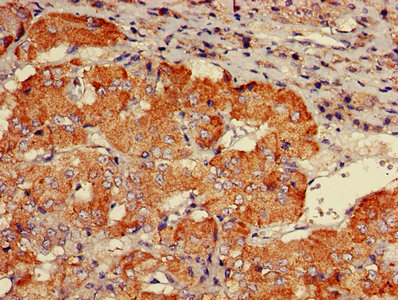

IHC image of CSB-PA860773LA01HU diluted at 1:600 and staining in paraffin-embedded human adrenal gland tissue performed on a Leica BondTM system. After dewaxing and hydration, antigen retrieval was mediated by high pressure in a citrate buffer (pH 6.0). Section was blocked with 10% normal goat serum 30min at RT. Then primary antibody (1% BSA) was incubated at 4°C overnight. The primary is detected by a biotinylated secondary antibody and visualized using an HRP conjugated SP system.